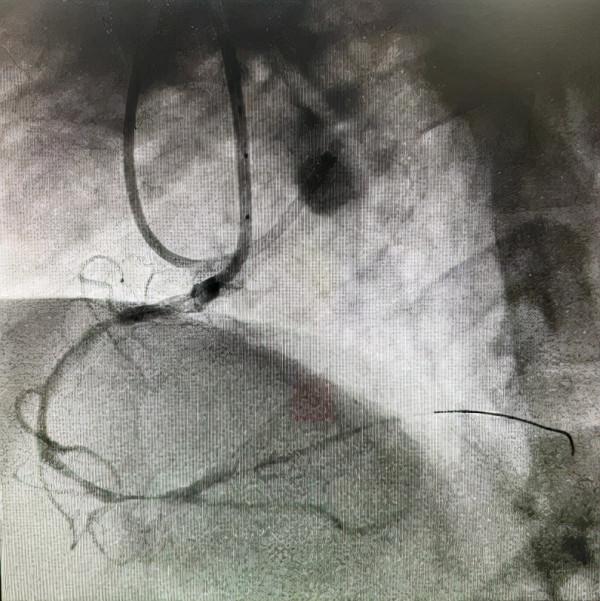

PCI過程:術中首先嚐試正向開通(AWE),逐步升級導絲,均多次進入內膜下,反覆嘗試不能送入遠端真腔,王健主任果斷啟動正向ADR技術,利用Corsair微導管於右冠近段製造正向夾層,使用專用器械Stingray球囊,Gaia Third導絲穿刺,

成功透過血管內膜下重新進入遠端血管真腔,經過多體位投照、逆向造影均證實為真腔,順利開通閉塞病變。

正向造影可見右冠全程瀰漫狹窄病變

序貫植入4枚第二代藥物洗脫支架覆蓋病變。